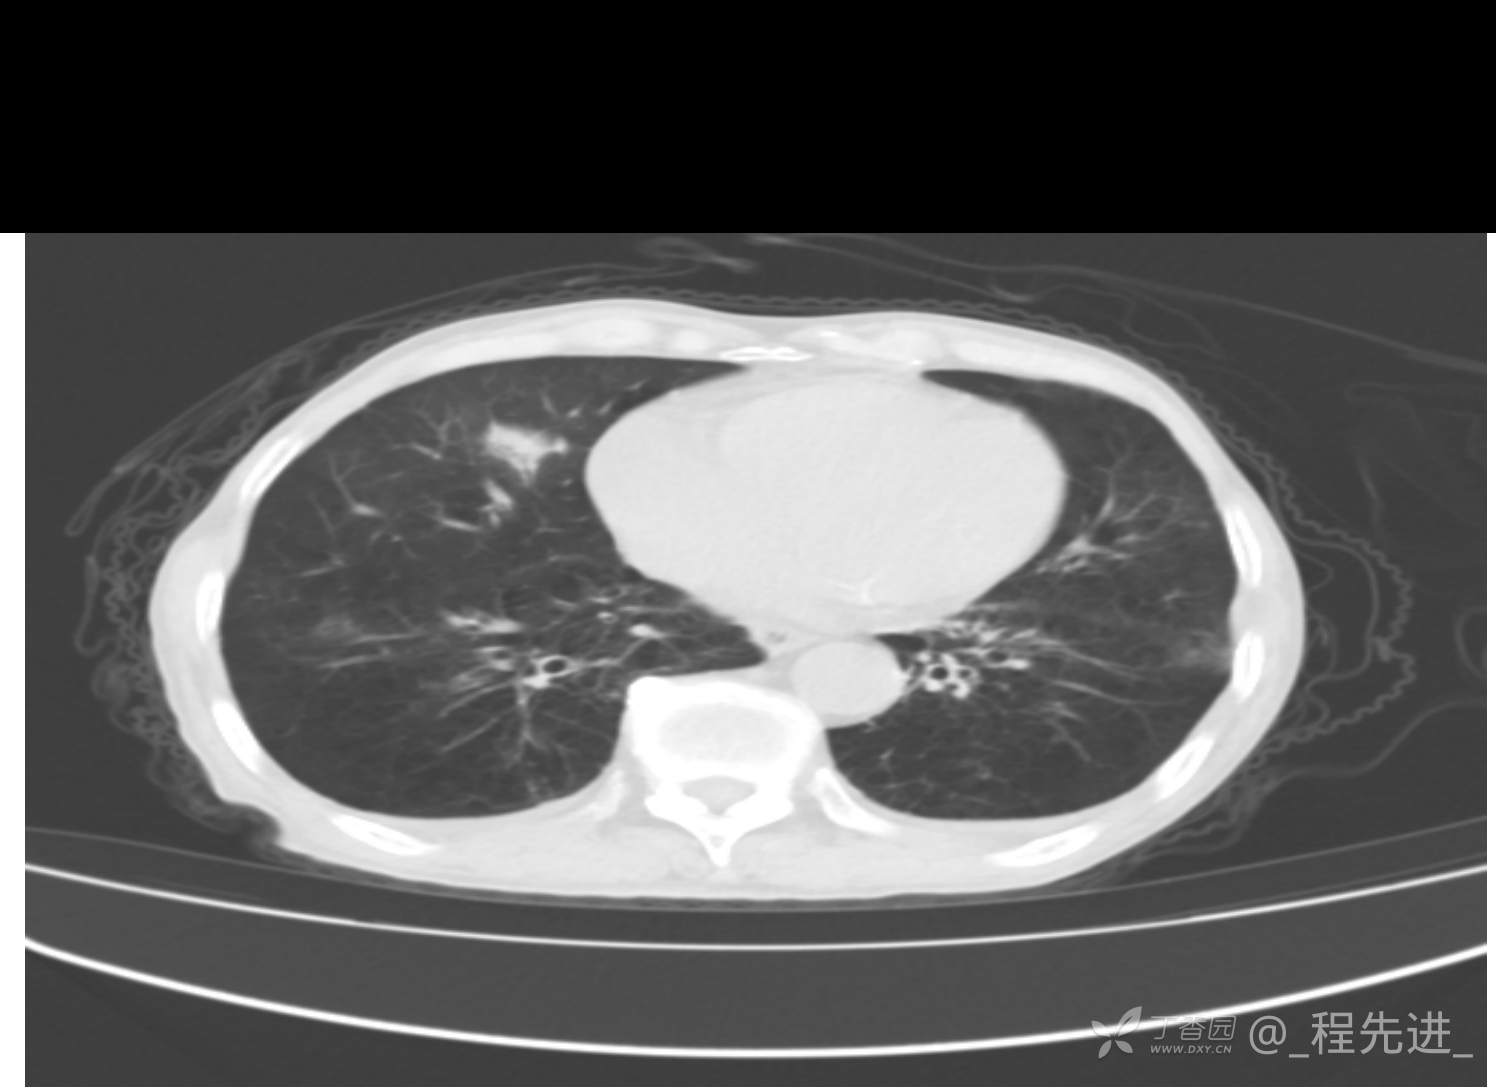

患者性别:男

患者年龄:81岁

简要病史:反复咳嗽、咳痰20余年,加重1周。两肺呼吸音低,可闻及散在干湿啰音。